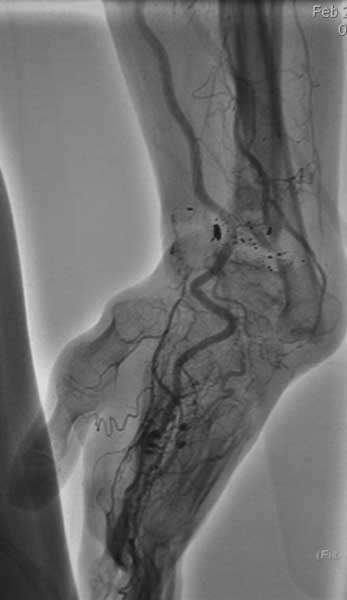

Изучали ли вы достаточно тщательно ангиограммы пораженного сегмента? Если да, то вы обратили внимание, что в артериальной фазе практически полностью отсутствует контрастирование лучевой артерии в зоне дефекта, тем самым вы имеете разорванную артериальную дугу и стабильный кровоток только в одном бассейне-локтевой артерии, тыльная межкостная не контрастировалась. Невзирая на это, вы предлагаете использовать пластику дефекта трансплантатом локтевой кости на сосудистом пучке (единственном, который объективно сохранился). Не боитесь ли вы возникновения проблем кровоснабжения кисти при выполнении данного вмешательства и как вы готовы бороться с этим (имею в виду оснащение, специалистов по микрохирургии и пр.)-это вопрос номер 2.